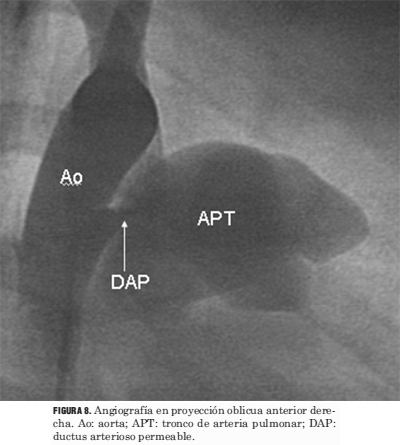

Doscientos setenta y cinco pacientes presentaban un DAP; sus edades estaban comprendidas entre 2 meses y 54 años y sus pesos entre 3,2 a 79 kg (tabla 2). El acceso percutáneo fue arterial o venoso femoral o ambos. Se realizó medida de la presión arterial pulmonar, cálculo de la relación QP/QS y de las resistencias pulmonares. Se llevó a cabo una aortografía para definir tipo anatómico y tamaño del DAP, lo que permitió elegir el dispositivo a usar (figura 8) (3). En 219 pacientes se utilizaron coils, en 55 Amplatzer PDA y en uno bolsa de Grifka.

Figura 8. Angiografía en proyección oblicua anterior derecha. Ao: aorta; APT: tronco de arteria pulmonar; DAP: ductus arterioso permeable.